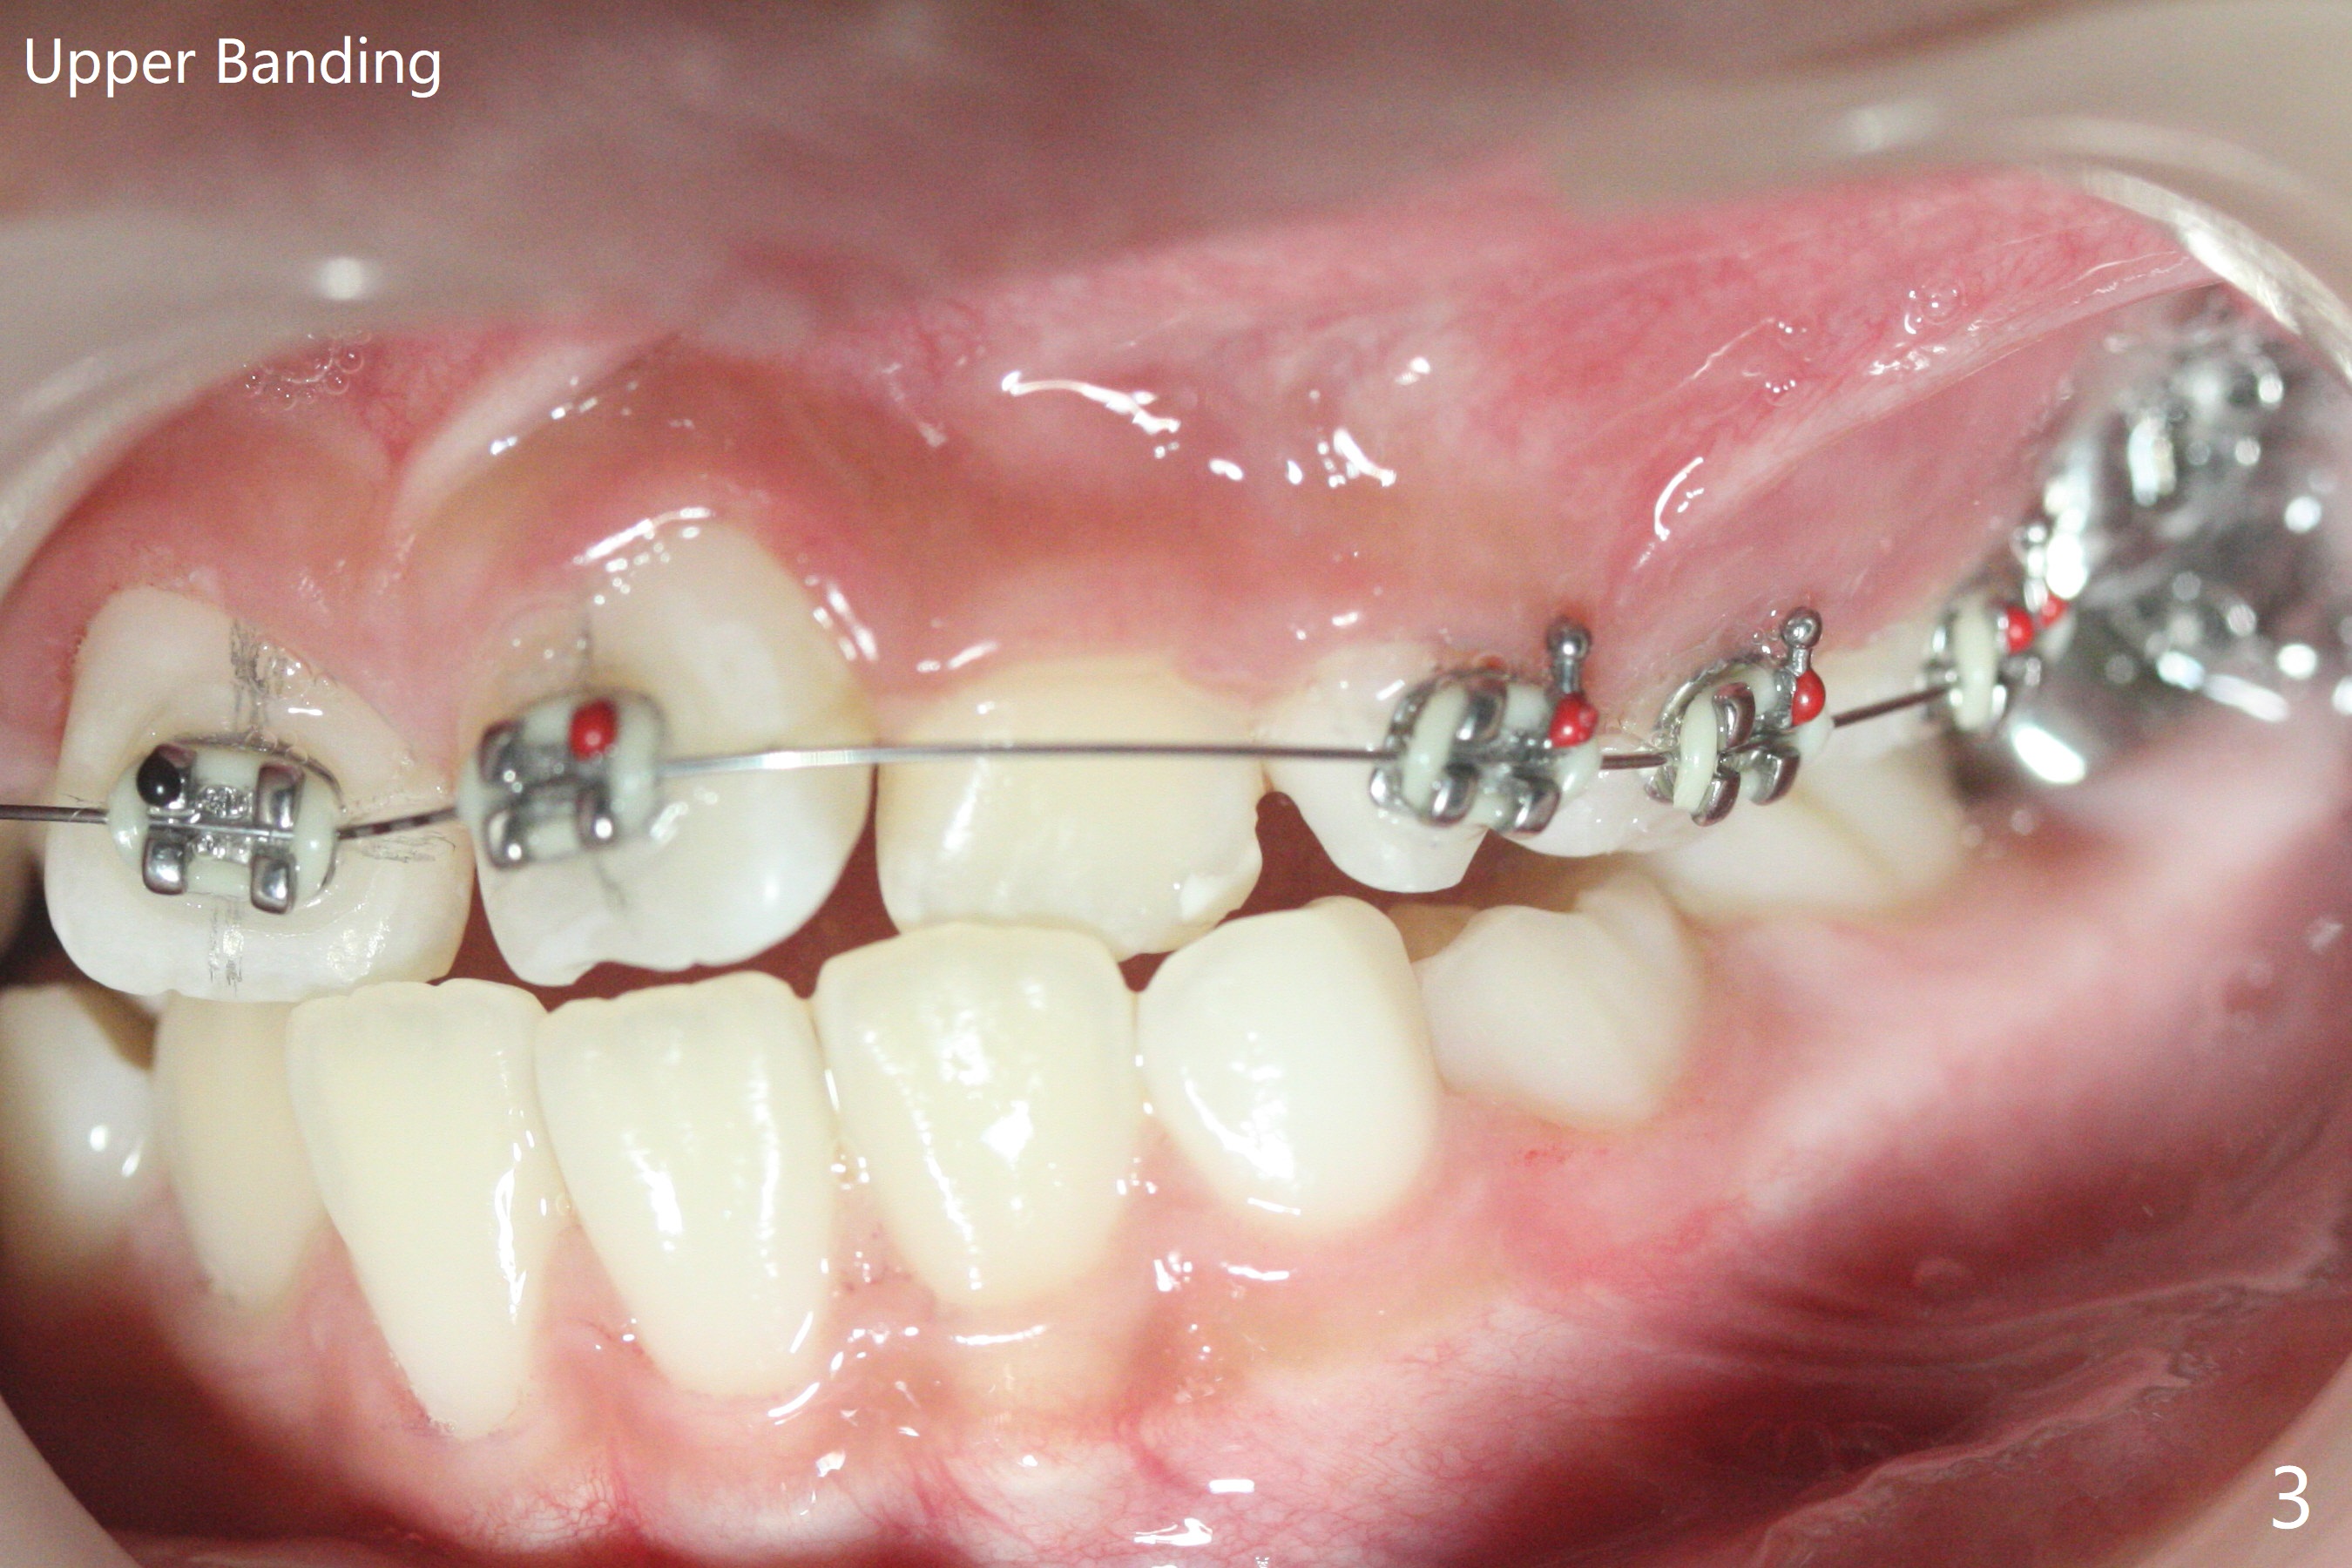

由于上颌拥挤严重,先放置矫正器(图一至三(.012));右上2空间小,可能需要从4近中片切获得,右边open coil spring应该比左边长。